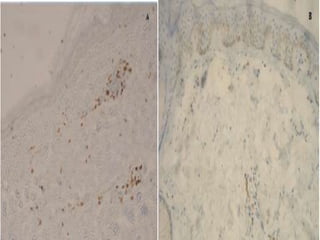

Melanocytes disappearance

(A) Immunohistochemistry with the melanocyte-

specific antibody NKI-beteb shows a partial

absence of melanocytes from perilesional

(PL) epidermis.

(B) CD3-immunoreactive T cells in PL skin.

CD1a-reactive Langerhans

• Basal localization of CD1a-reactive Langerhans

cells in the lesional (L) epidermis of a vitiligo

donor.

ICAM-1 reactivity in PL skin

• ICAM-1 reactivity in PL skin of vitiligo donor.

Note: the focal epidermal expression (arrow).